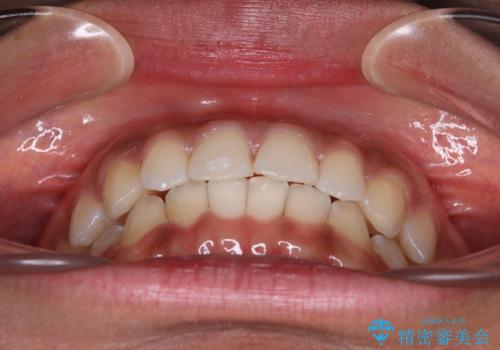

- 上下前歯の叢生を気にして来院された患者様です。

インビザラインでの治療を希望されていて、デコボコの程度が中等度であり、安価なパッケージにて対応可能と判断されたため、インビザライン・モデレートを用いて矯正治療を行うこととしました。

インビザライン・モデレートは、製作できるアライナーの枚数に制限があるため、移動可能な量に限りがあるものの、インビザライン・ライトよりも枚数が多いため、幅広い症例に対応可能です。